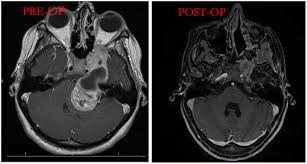

Trastornos de la base del cráneo

Puede ocurrir una amplia variedad de tumores dentro de la base del cráneo, incluidos los tumores que surgen del cerebro, el revestimiento del cerebro, los huesos de la base del cráneo o la glándula pituitaria. La base del cráneo también puede desarrollar tumores metastásicos, que se originan a partir de cánceres en otras partes del cuerpo.

Los pacientes con un tumor de la base del cráneo pueden experimentar síntomas como dolor y entumecimiento facial, dolor de cabeza, obstrucción nasal, dificultad para respirar, pérdida de audición y otros, dependiendo del tipo y tamaño del tumor. Los tumores de la base del cráneo se clasifican por su ubicación o tipo y pueden incluir meningiomas, schwannomas, cordomas y tumores metastásicos que se han diseminado desde otras áreas del cuerpo.

sean benignos o malignos, casi todos los tumores de la base del cráneo requieren tratamiento para extirpar el tumor y prevenir complicaciones a medida que el tumor crece o se propaga. El tratamiento para los tumores de la base del cráneo puede incluir cirugía, radioterapia, radiocirugía, quimioterapia o una combinación de estos enfoques.